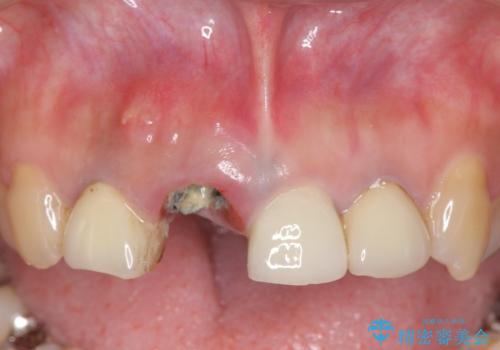

- 右上の前歯が折れてしまったので診て欲しいといらっしゃった方の症例です。

右上1番目の歯は保存不可能だったため抜歯し、ブリッジによる補綴を行いました。